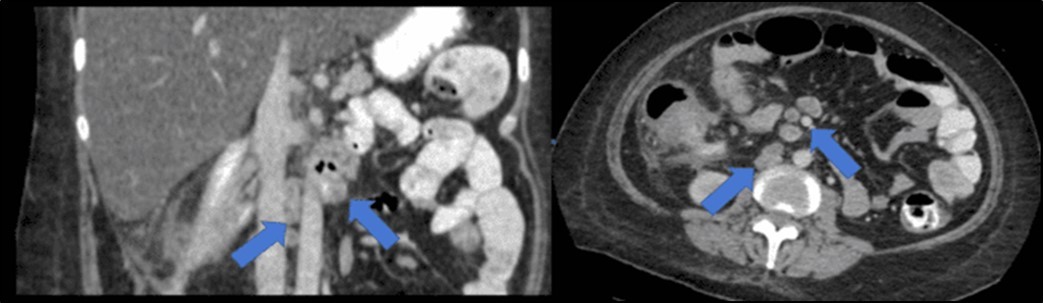

There was no evidence of malignancy or IBD seen during both endoscopic procedures. Computed tomography (CT) scan of the whole abdomen was done which showed inflammatory changes involving the cecum and adjacent duodenum and ileum with coloenteric fistulae. There was noted progression of abdominal lymphadenopathies as well as ascites. Main consideration was an infectious disease process (i.e. TB) (Figure 2, Figure 3, Figure 4 to Figure 5).

Figure 3.Coronal and axial view of the abdomen, the blue arrows pointing towards the suggestive communication to the ileum.

Coronal and axial view of the abdomen, the blue arrows pointing towards the suggestive                     communication to the ileum.

Figure 4.Coronal and axial view of the abdomen, the blue arrows pointing towards the suggestive communication to the duodenum

Coronal and axial view of the abdomen, the blue arrows pointing towards the suggestive             communication to the duodenum

Figure 5.Enlarged and necrotic abdominal nodes in the mesenteric, pericecal, pericolic, para-aortic, paracaval and inter-aortocaval regions. Prominent and enlarged nodes also located in the common hepatic and periportal regions

Enlarged and necrotic abdominal nodes in the mesenteric, pericecal, pericolic, para-aortic, paracaval and inter-aortocaval regions. Prominent and enlarged nodes also located in the common hepatic and periportal regions